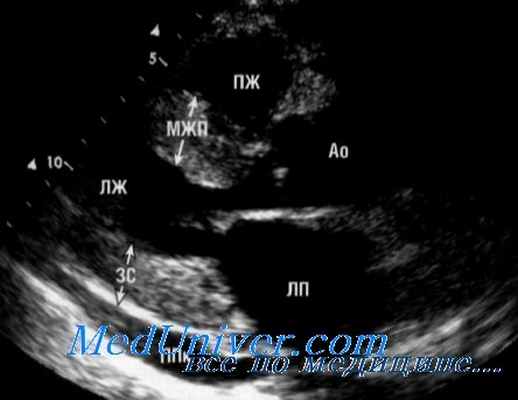

| ЭхоКГ | Нормальная толщина стенок. Утолщение перикарда. Парадоксальное движение МЖП в раннюю диастолу | Увеличение толщины стенок (амилоидоз). Увеличение ЛП и ПП |

А - М-режим ЭхоКГ из парастернальной позиции. Представлены типичные особенности констриктивного перикардита, инцизура МЖП (показана стрелкой), и выравнивание задней стенки ЛЖ.